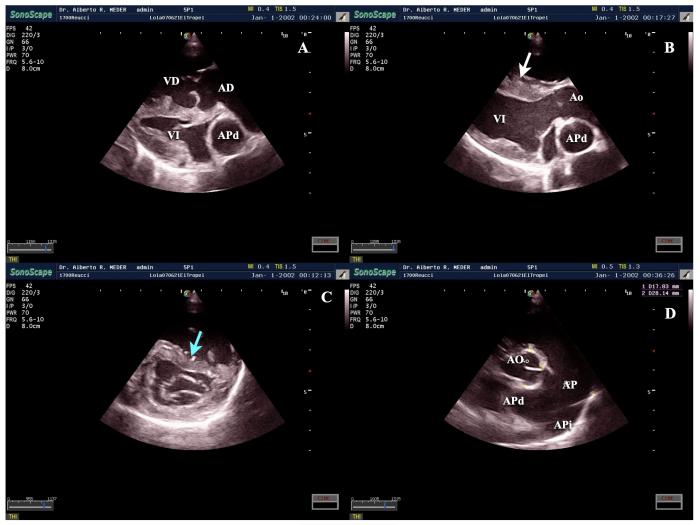

En las imágenes bidimensionales, la HP evidencia sobrecarga de volumen y presión del ventrículo derecho, aplanamiento sistólico del septo interventricular hacia la izquierda, dilatación anular tricuspídea con aparato valvular normal, arqueamiento septal atrial hacia la izquierda, dilatación del anillo pulmonar asociada a convexidad de valvas pulmonares hacia el ventrículo derecho y arteria pulmonar y ramas derecha e izquierda, dilatadas en comparación con la aorta como patrón de referencia8,9,19(Figura3). La exploración en modo M muestra aumento del diámetro del ventrículo derecho y aplanamiento septal o, en casos más graves, movimiento septal paradójico11.